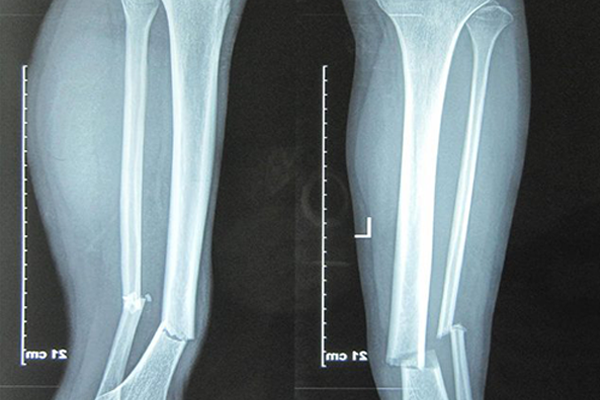

Thông qua hình ảnh phim chụp X-quang

Để quan sát được rõ nét và chính xác quá trình liền xương, các bác sĩ sẽ chỉ định người bệnh tiến hành chụp X-quang vị trí gãy để thấy rõ tình trạng hiện tại để đưa ra những kết luận chính xác.

Thông qua hình ảnh chụp X-quang có thể phát hiện được tình trạng chậm liền xương